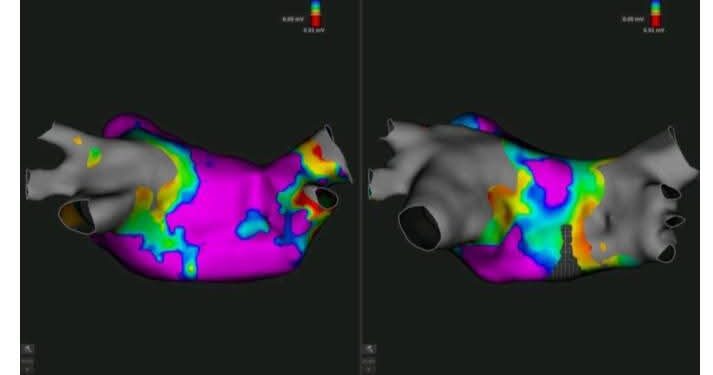

نجح الفريق الطبي بالمستشفى الجامعي سهلول، يوم الأربعاء 4 فيفري 2025، في إجراء أول عملية لاستئصال اضطرابات نبضات القلب باستخدام نظام “Rythmia” المتطور، الذي يتيح تشخيصًا دقيقًا وعلاجًا موجّهًا لهذه الحالات المعقدة.

واجرى هذه العملية، الأستاذ إلياس النفاتي، رئيس قسم جراحة القلب والشرايين، والأستاذ وليد نعيجة، رئيس قسم التخدير والإنعاش، وفق بلاغ صادر عن وزارة الصحة، اليوم الخميس 6 فيفري 2025.